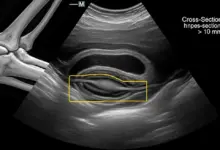

Importância da Eletroneuromiografia no Entendimento da Causa

Para diagnósticos mais precisos, a eletroneuromiografia é muito importante, já que esse exame verifica a saúde de nervos e músculos.

Através da eletroneuromiografia, é possível detectar casos de tendinite, o que a diferencia de outras doenças que causam sintomas parecidos.

Com o exame, identifica-se a causa real da dormência nas mãos. Assim, o médico pode orientar corretamente o tratamento para tendinite no ombro, assim como recomendar formas de prevenir o problema.